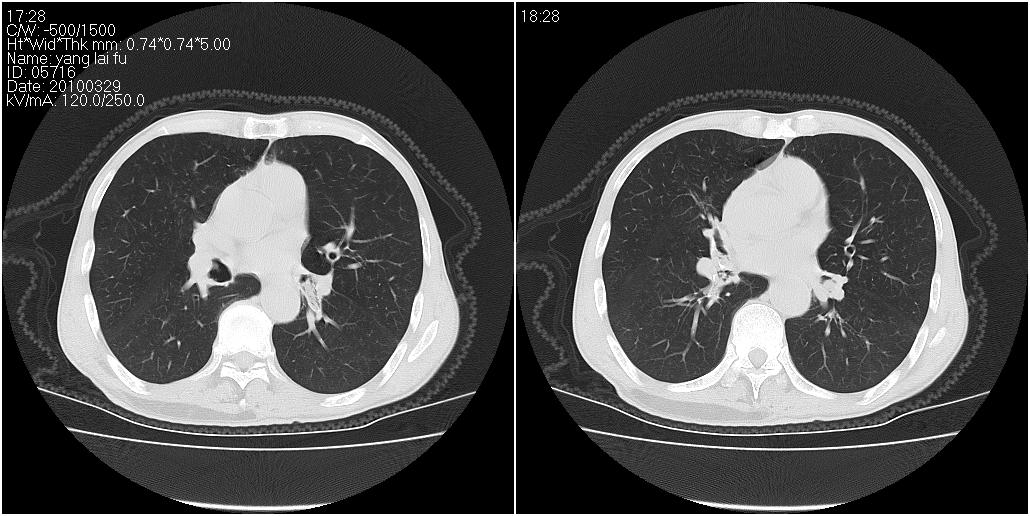

标题: CT25416:男性,70岁。胸片发现右下肺斑片状阴影 [打印本页]

标题: CT25416:男性,70岁。胸片发现右下肺斑片状阴影

以下是ct检查的情况:

考虑右肺下叶炎症可能性大?未除占位,建议增强。右下肺肺不张

右下胸壁皮下气肿。